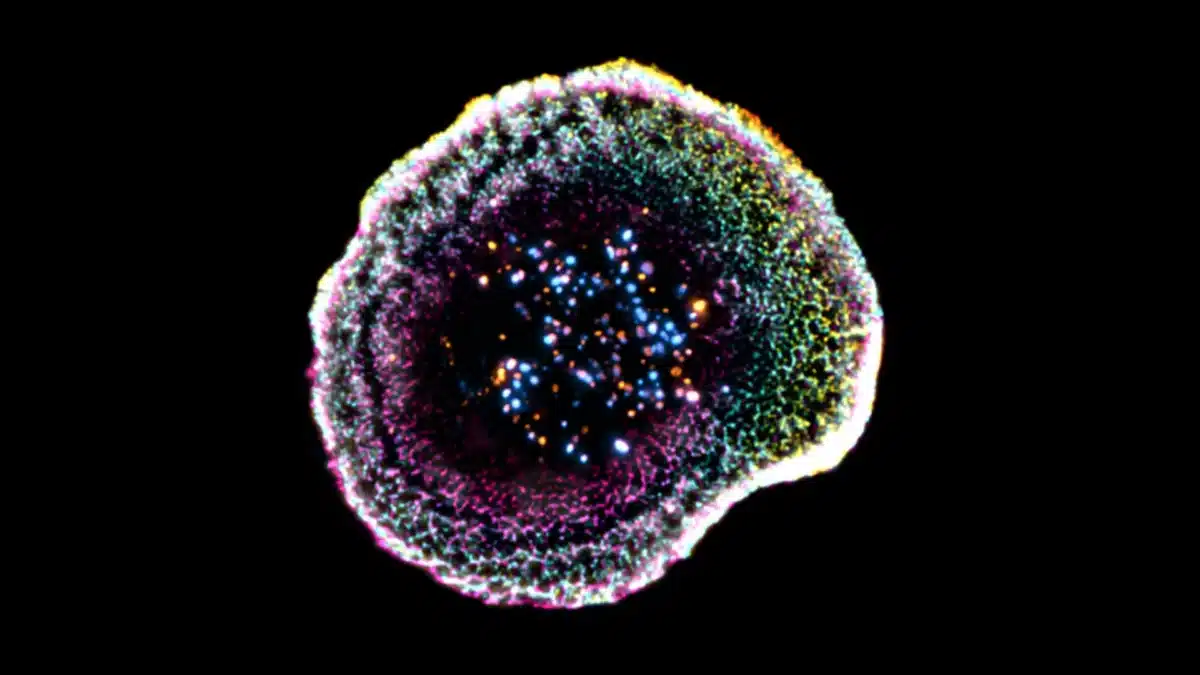

Imagen; una célula T citotóxica captada mediante microscopía de criocontracción (cryo-ExM). Los puntos de colores que se observan en el centro son gránulos citotóxicos que se utilizan para destruir células infectadas o cancerosas. © F. Lemaitre @ UNIGE

Publicadas las primeras imágenes tridimensionales de la sinapsis inmunológica, la diminuta zona de contacto ultraorganizada que los linfocitos T citotóxicos forman para destruir células cancerosas sin atacar a las células vecinas

Cuando un linfocito T reconoce una célula cancerosa, no simplemente le dispara toxinas al azar. Forma una estructura de contacto altamente organizada llamada sinapsis inmunológica. Aquí las proteínas se disponen en capas concéntricas con una geometría casi perfecta. En el centro se concentran los receptores que reconocen a la célula enemiga. Alrededor, en un anillo, se sitúan las moléculas de adhesión que mantienen el contacto; en el perímetro exterior, las proteínas de señalización. Esta arquitectura permite a la célula T dirigir sus «cargas» letales (perforinas y granzimas) exactamente hacia la célula diana, sin que escapen hacia el tejido circundante.

Las primeras imágenes 3D completas de la sinapsis inmunológica publicadas en Cell Reports confirman y amplían la arquitectura conocida, pero también revelan detalles inesperados. Las perforinas, las proteínas que literalmente perforan la membrana de la célula diana para introducir las granzimas que la matarán, se organizan en estructuras semiesféricas que apuntan exclusivamente hacia la célula objetivo. Esta geometría explica por qué el linfocito T puede matar con tanta precisión sin generar daño colateral: las toxinas viajan en una dirección definida por la arquitectura tridimensional de la sinapsis.